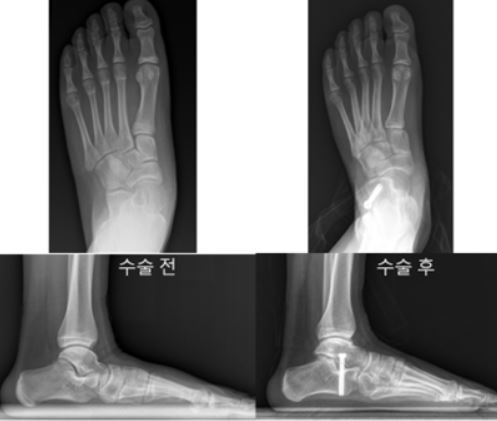

특발성 평발은 특별한 외상이나 질병 없이 성장기 아동에게 발생하는 발 모양의 변화를 말한다. 발바닥 아치가 무너지고 발이 안쪽으로 꺾이는 구조적 이상이 나타나며, 체중이 실리면 통증, 보행 이상 등을 유발할 수 있다. 대부분은 깔창 착용이나 스트레칭 운동과 같은 보존적 치료로 증상이 완화되지만, 증상이 지속되거나 변형이 심한 경우에는 수술을 고려하게 된다. ‘종골 정지술’을 받은 12세 환아의 수술 전(왼쪽)과 수술 3년 후 방사선 사진. 수술 후 발의 정렬이 정상에 가깝게 교정됐으며, 아치가 회복돼 평발 변형이 효과적으로 교정된 모습을 확인할 수 있다.

대표적으로 시행되는 ‘종골 연장술’은 뒷꿈치뼈(종골)를 절골한 뒤 뼈를 이식해 아치를 복원하는 수술로, 한 번의 수술로도 지속적인 교정 효과를 얻을 수 있다. 또 다른 수술법인 ‘종골 정지술’은 나사 1개를 삽입해 평발을 교정하는 방식으로, 보다 간단한 수술이 가능하다는 점이 특징이다. 두 수술 모두 평발 교정에 효과적인 것으로 알려져 있지만, 실제 환자 데이터를 바탕으로 두 수술법의 치료 결과를 비교한 연구는 거의 없었다.

연구팀은 두 수술법의 치료 결과를 비교하기 위해 2003년부터 2022년까지 평발 교정 수술을 받은 10~14세 소아 환자 127명(총 223족)을 대상으로 연구를 진행했다. 수술 전후의 발 모양과 기능 변화를 확인하고자 방사선 사진과 삶의 질 평가 설문(OAFQ)을 통해 분석하고, 회복 기간과 합병증 발생 여부를 함께 비교했다.

연구 결과, 두 수술법 모두 평발을 교정하는 데 효과적인 것으로 나타났다. 두 환자군 모두에서 발 아치와 정렬을 나타내는 방사선 사진 수치들이 수술 후 크게 개선됐다. 삶의 질 평가에서도 신체 기능, 학교생활 및 놀이, 정서적 측면, 신발 착용 등 모든 영역에서 점수가 향상된 것을 확인할 수 있었다.